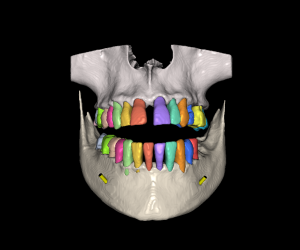

Curso Exoplan BASIC

Carga de la ficha y base de datos (DentalDB)

Manejo del software / Herramientas

Planificación

Guide creator

Curso Exoplan PRO

Curso Exoplan BASIC (Incluido)

Técnica Doble Dicom

Técnica Dicom Stl

Curso Flujo Exocad / Exoplan

Curso integración avanzado para dentistas (incluido)

Curso Exoplan PRO (incluido)

Dirigido a Dentistas los cuales quieran realizar la planificación y diseño del encerado, colocación de implantes Full Mouth y carga inmediata o diferida.

Curso Bluesky Plan Avanzado

Requiere Curso Bluesky Plan Básico o manejo demostrable Diseño y colocación de implantes / Fabricación de guía quirúrgica Pilares personalizados y posicionadores Técnica Doble Dicom / Técnica Dicom Stl Guia de recorte óseo https://www.blueskyplan.com/...

Curso Bluesky Plan Básico/ Intermedio

Manejo y herramientas básicas del software Diseño y colocación de implantes Fabricación de guía quirúrgica https://www.blueskyplan.com/